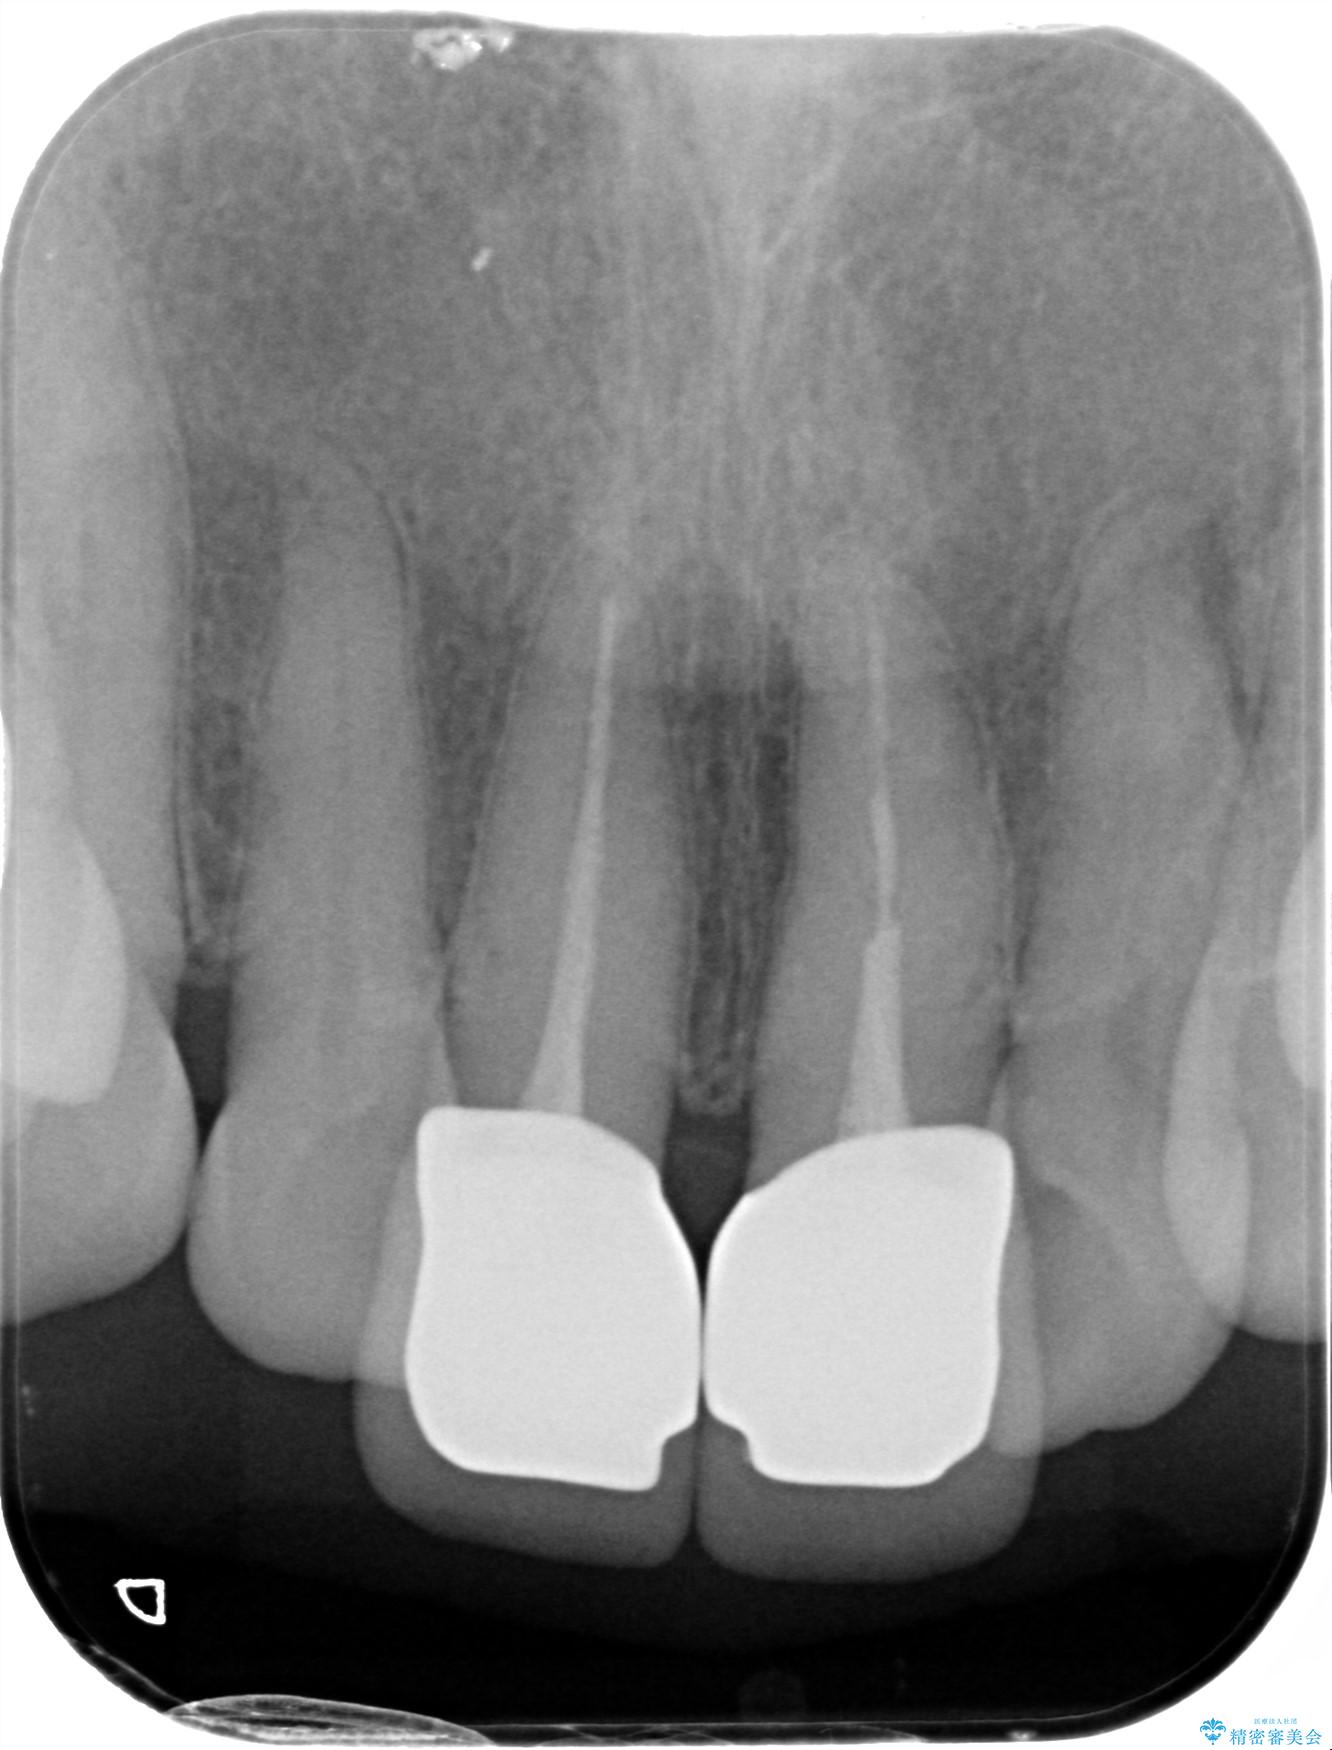

根管治療は行わず、クラウンのやり替えのみ行います。

審美性に優れるジルコニアクラウンによる治療を計画します。

26.4万円(ジルコニアクラウン×2・仮歯×2)